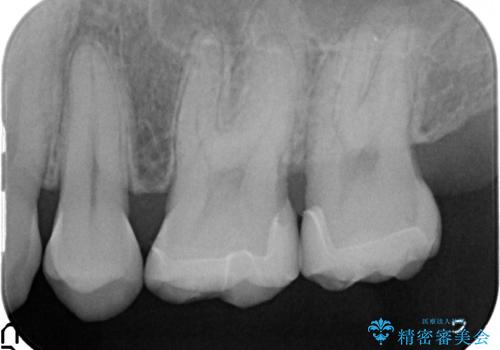

- 左上奥歯がしみるといらっしゃった方の症例です。

左上7近心の虫歯は歯茎より深く、歯茎を下げるため歯周外科を行いました。

術後歯肉の回復を待ち、左下6、7ともにセラミックインレーによる修復を行いました。